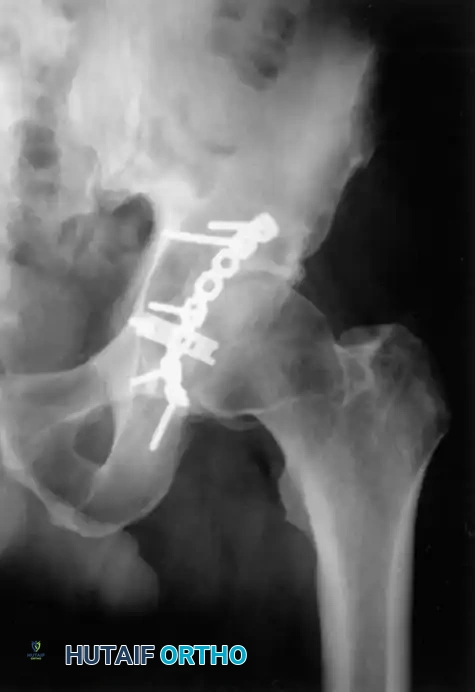

Associated Surgical & Radiographic Imaging

Hutaifortho's Orthopaedic Diagram